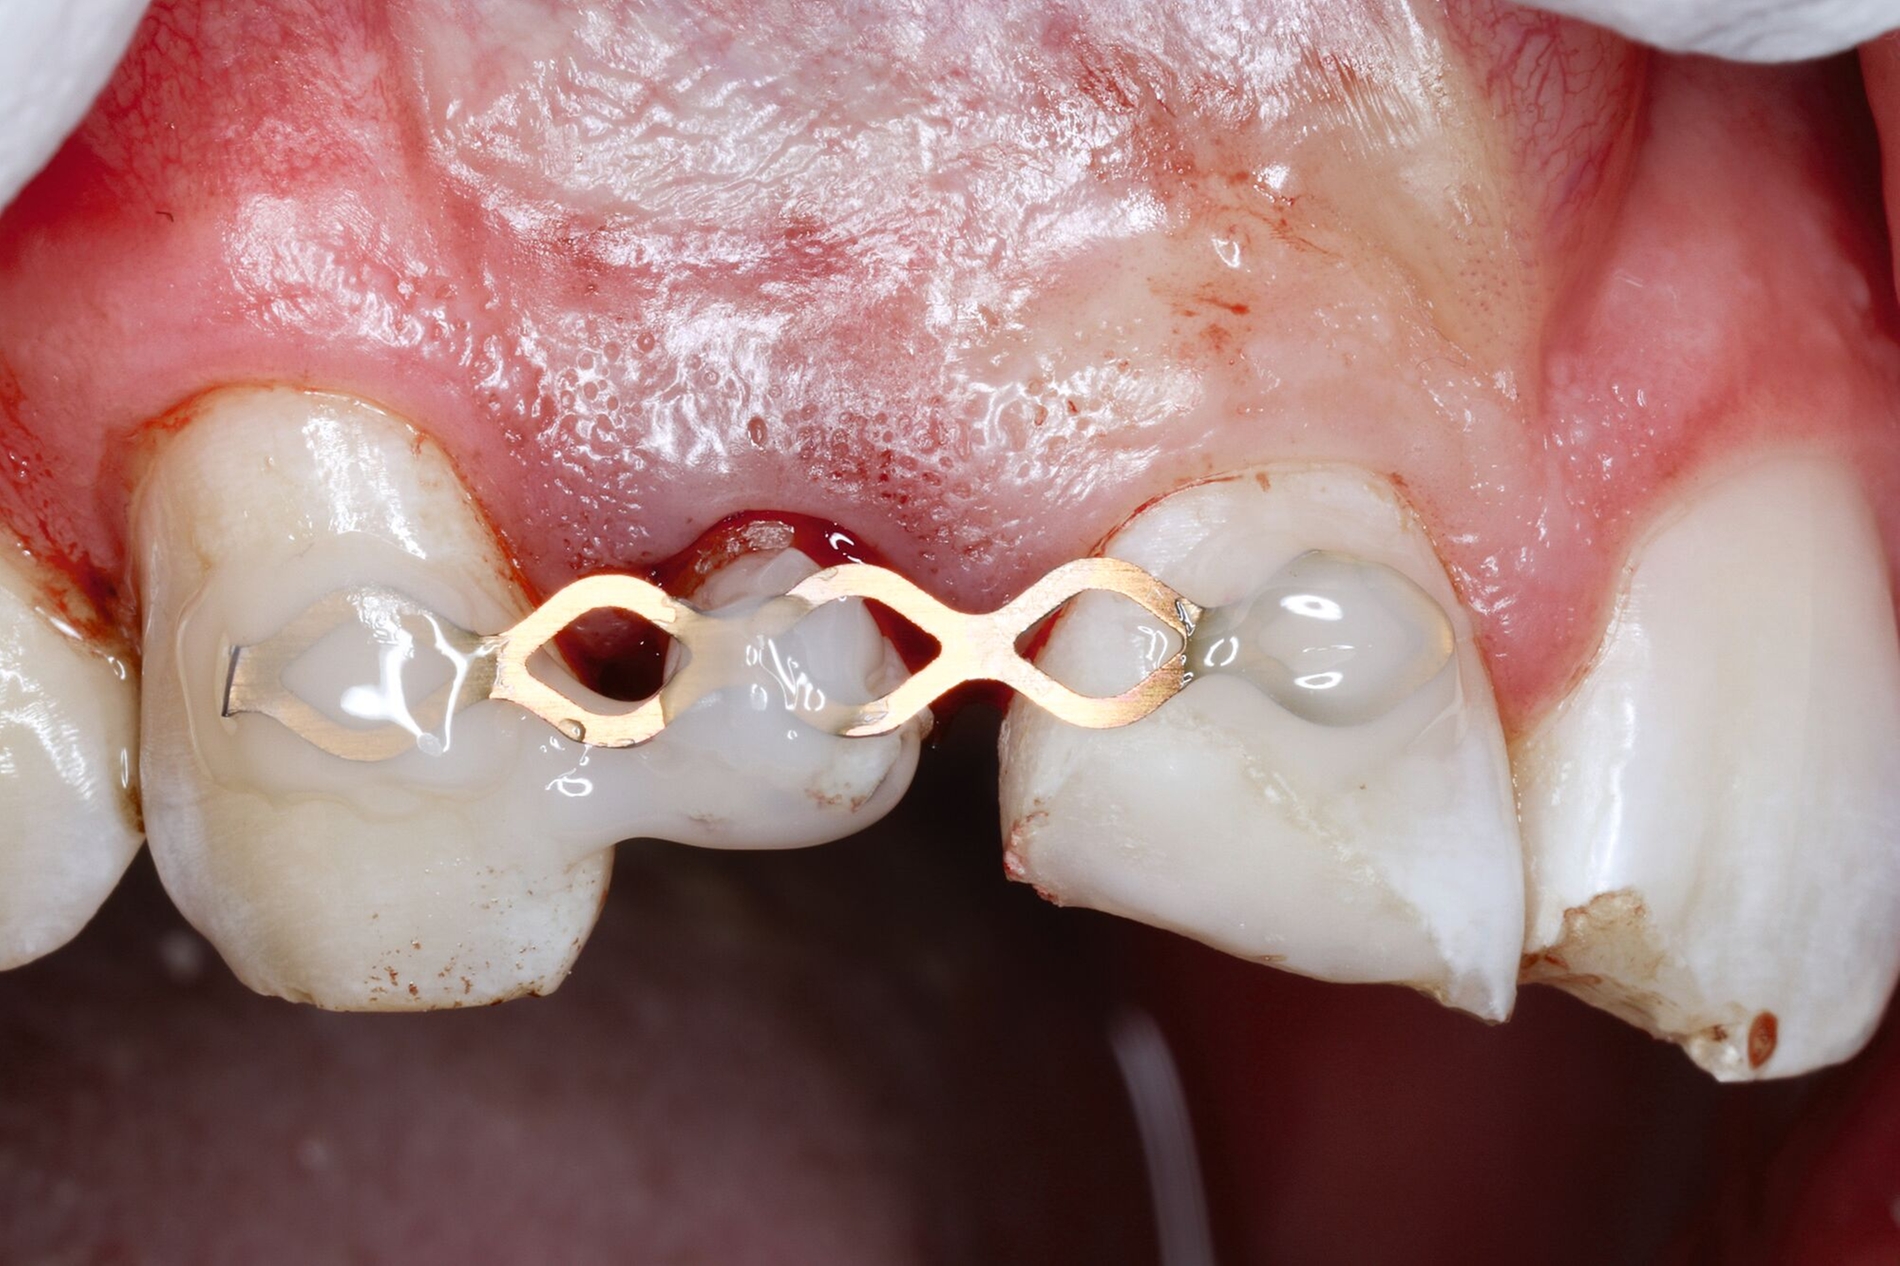

Wenn die Lückenversorgung durch eine Transplantation (siehe Teil 4 der Fortbildung „Dentales Trauma“: Chirurgische Aspekte) oder einen kieferorthopädischen Lückenschluss (siehe Teil 5 der Fortbildung „Dentales Trauma“: Kieferorthopädische Aspekte) vorbereitet wurde, beschränkt sich die restaurative Versorgung auf eine Formkorrektur der Zähne. Diese kann – je nach Situation und Präferenz des Behandlers – mit direkten (Abbildung 4) oder mit (minimalinvasiven) indirekten Restaurationen (Veneers, Teilkronen) erfolgen. Gerade bei jungen Patienten muss allerdings berücksichtigt werden, dass im Zuge der passiven Eruption [Mele et al., 2018] Veränderungen des Gingivaverlaufs an den restaurierten Zähnen zur Exposition der Restaurationsränder führen und eine neue Versorgung nach mehreren Jahren erforderlich machen können.